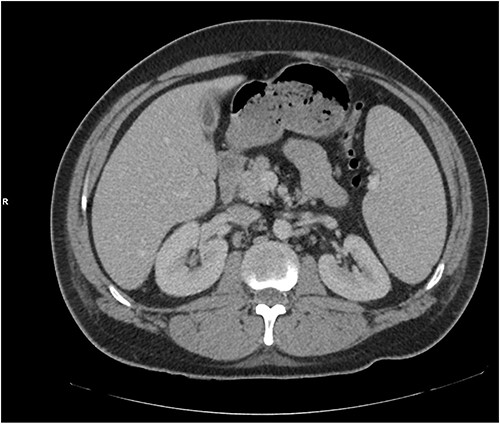

He presented with right sided abdominal pain associated with jaundice, fever, myalgia and arthralgia after receiving his second dose of the penultimate cycle of intra-renal BCG instillation. He did not have any tuberculosis contacts. His parameters on admission were stable. C-reactive protein levels were 230 mg/l and white cell count (WCC) was 6.51 × 109/l. His liver function tests were deranged, with a mixed obstructive and hepatitic picture. A CT kidneys, ureters and bladder (KUB) showed mild diffuse dilatation of the right ureter and renal pelvis with minimal amount of peri-ureteric fat stranding (Fig. 1). A CT scan of the abdomen with intravenous contrast (IV) was performed, this showed a distended right ureter down to the vesicoureteric junction, peri-ureteric fat stranding and lymphadenopathy in the aorto-caval space together with splenomegaly and atelectatic changes (Fig. 2).

An initial CT KUB showed mild diffuse dilatation of the right renal pelvis (as indicated by the arrow).